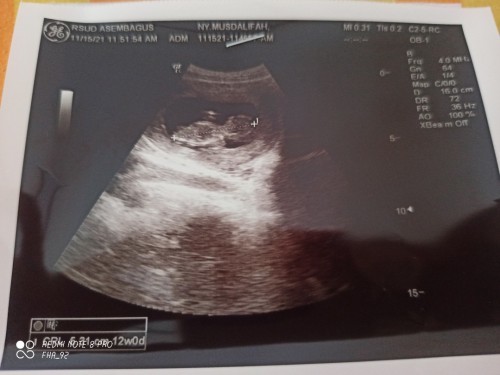

liat yg ada angka trus ada w dan d nya, tuh di pojok kiri bawah bun.. w : week d : day 12w0d berarti 12minggu0hari = 12minggu pas = kurang lebih 2 bulan bun selamaaat, sehat terus bunda da detuun❤

Baca lagiitu dibawah yg ketutupan watermark Redmi. bsk2 kalo letaknya atau kodenya berubah, pokonya bunda cari yg formatnya xxWxxD, kayak disitu 12W0D berarti 12minggu pas

halo bunda.. untuk melihat usia kehamilan, bunda bisa lihat tulisan CRL di bagian kiri bawah foto USG tsb.. usia kehamilannya 12w Bun..

12 minggu bu Musdalifah Next time, jangan segan2 tanya ke dokter nya bu. Kan masa pulang USG, usia kandungannya aja ga tau.

itu kn tertulis.12w0d. artinya 12minggu. 2,5bln. kurang lebih nya. blm.full 3bln.

12w mom, ada di sebelah kiri bawah ya deket watermark redmi